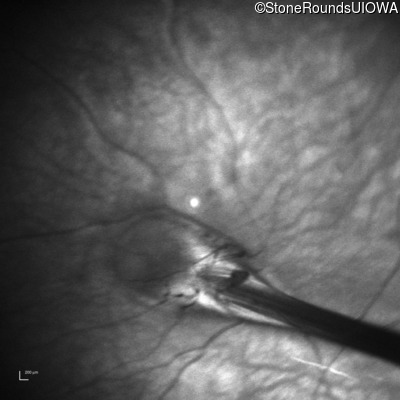

Infrared Fundus Photograph - Right - 10/200

Exemplar